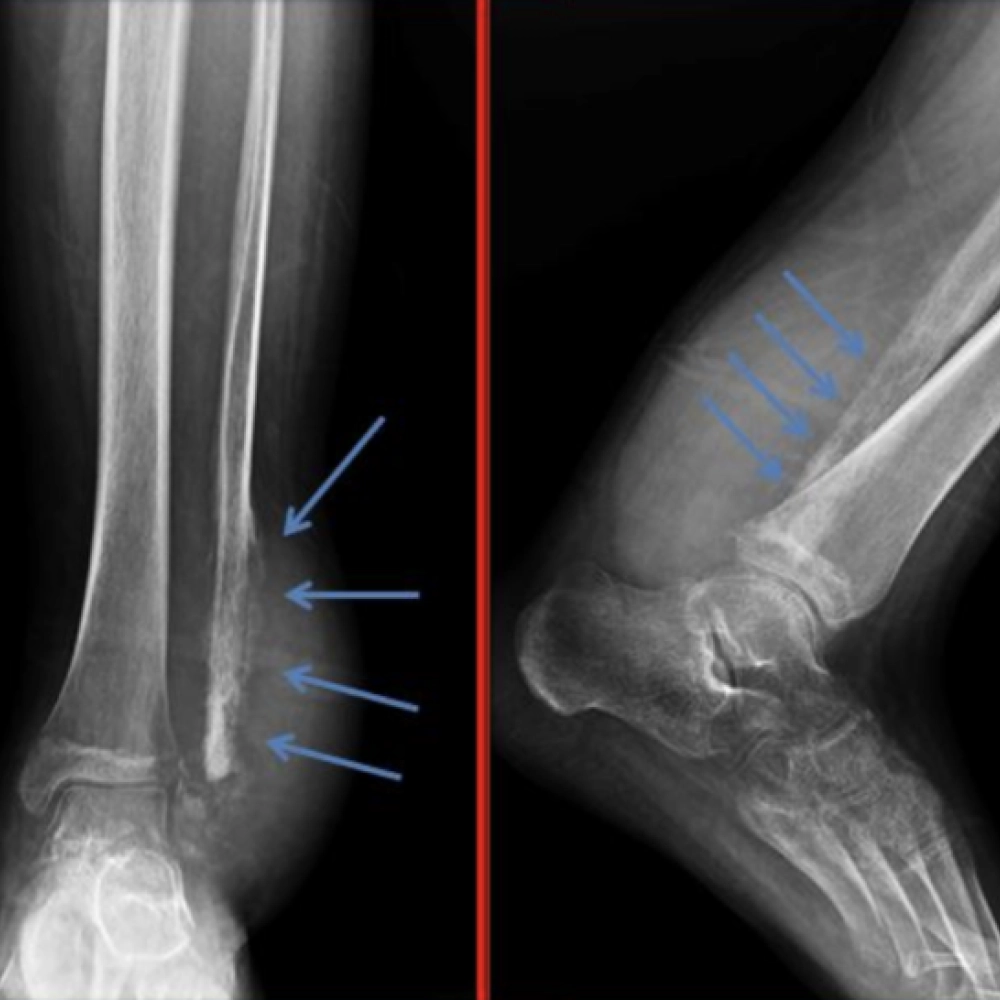

• Osteosarkom, kemik dokusundan kaynaklanan nadir bir kanser türüdür.

Kemiğin dördüncü en sık görülen primer malign tümörüdür.

Kromozom anomalisi söz konusudur.

Osteosarkom Nedir ve Tedavisi

Osteosarkom, mikroskobik düzeyde incelendiğinde immatür kemik üretiminin olduğu, sıklıkla kemikten o...